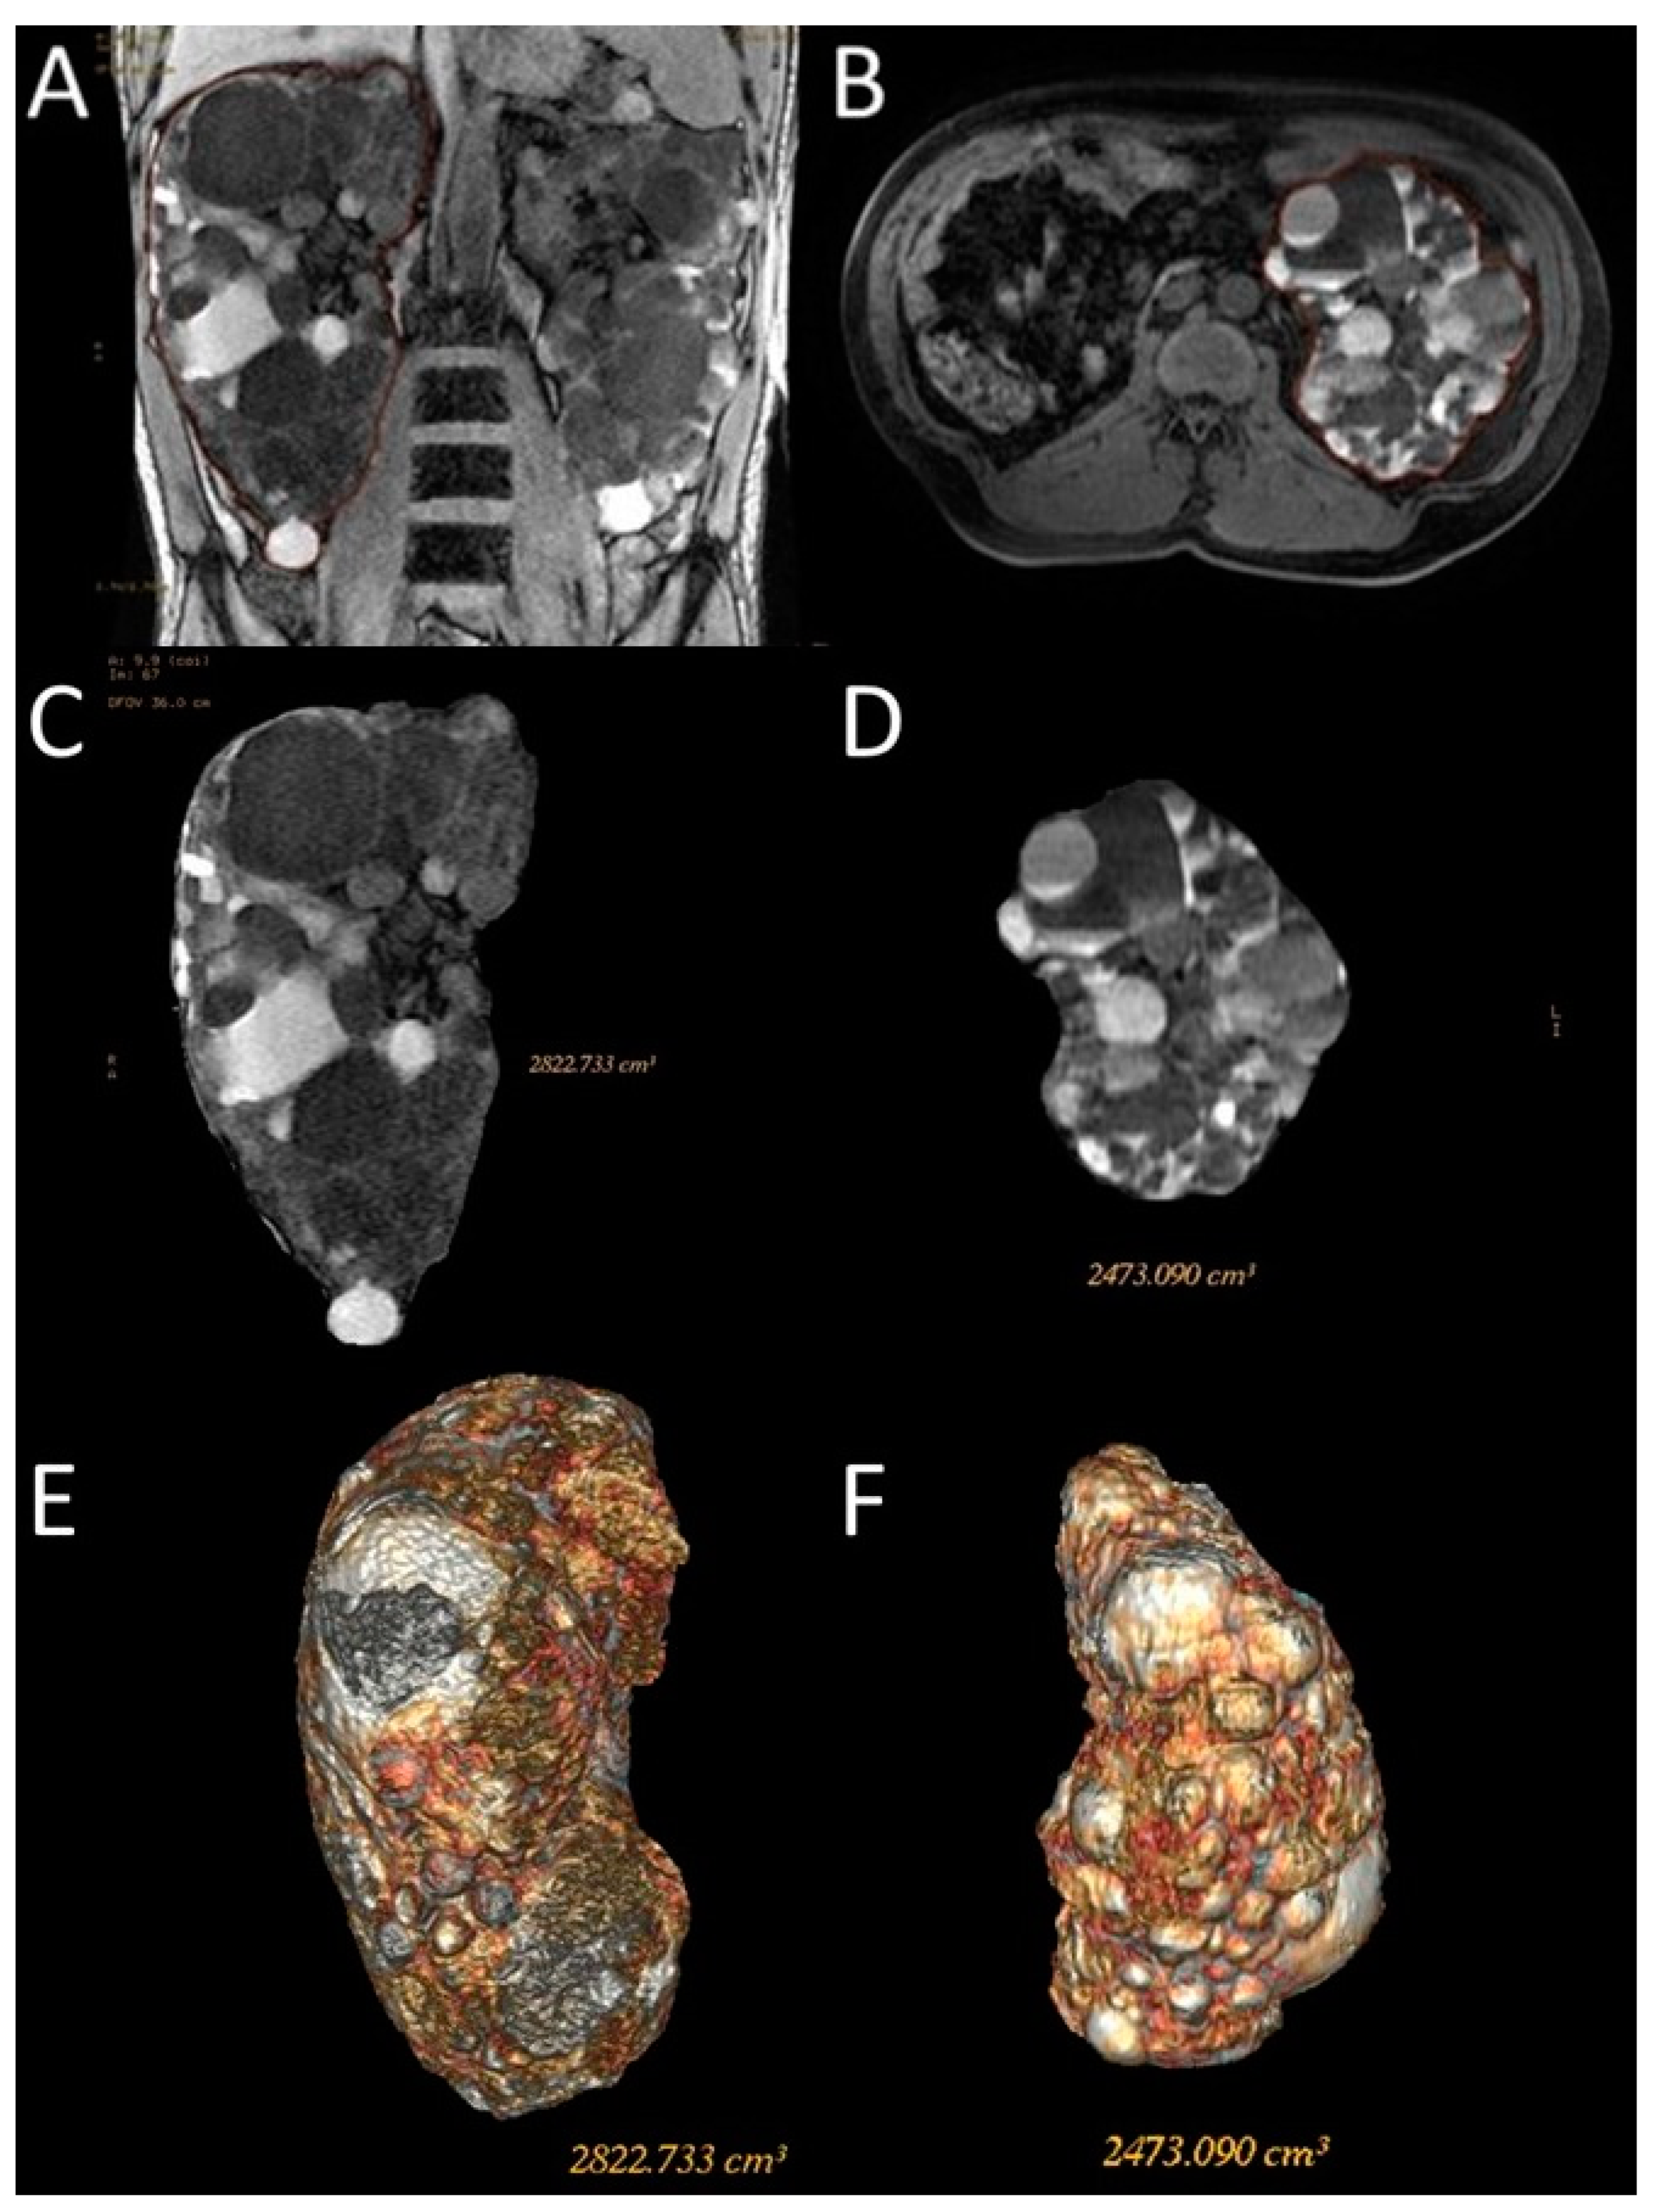

Figure 3.

Representative images of the semi-automatic volumetric segmentation method performed on two different patients. This method requires manual tracing of renal contours on some images—Coronal 3D Dual Echo (A) or axial LAVA (B)—with automatic reconstruction in the intermediate images. Extraction of the segmented kidney volume with SKV computation on the same contour plane (C,D) and reconstruction in volume rendering (E,F).

For this type of segmentation, the 3D sequences were selected; Coronal 3D T1 Dual Echo acquisitions were preferred for the shorter time requirement for semi-automatic segmentation; however, sometimes, due to the presence of motion artifacts or for greater operator confidence, the axial LAVA sequences were used. Both operators used the same sequence on the same patient to perform the semi-automatic volumetric segmentation.